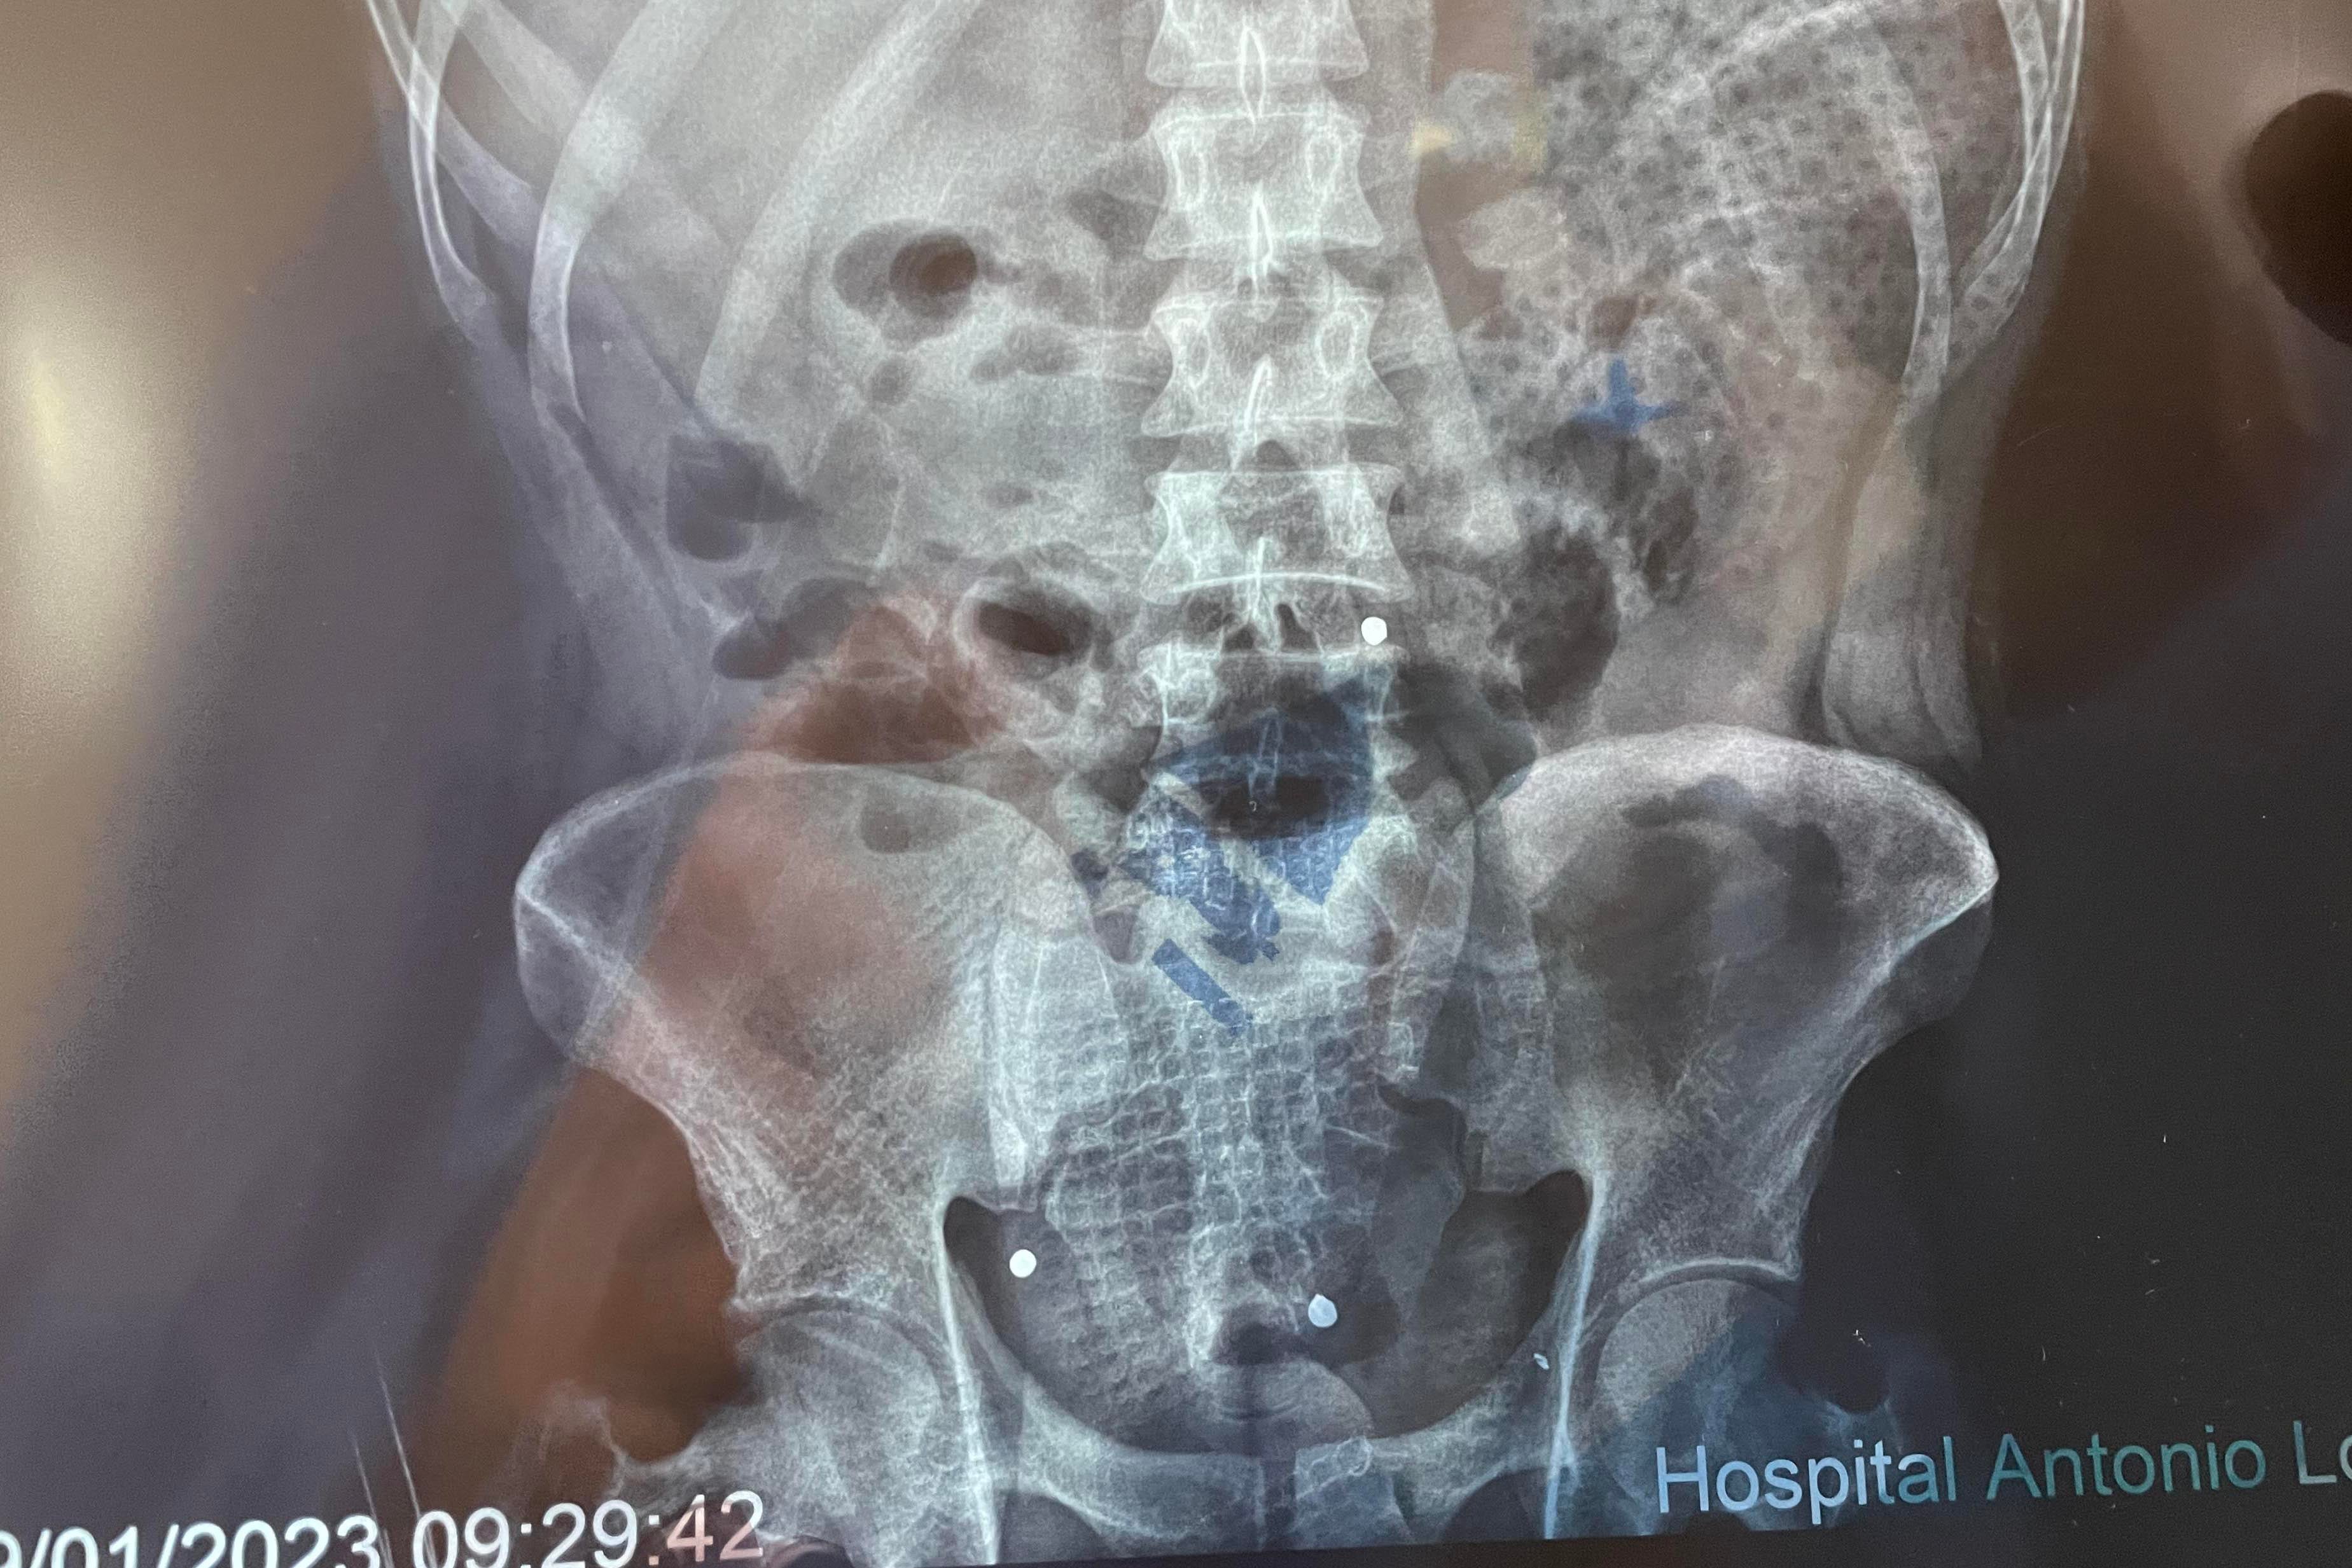

Una radiografía muestra tres de los cinco perdigones que impactaron a Quispe.